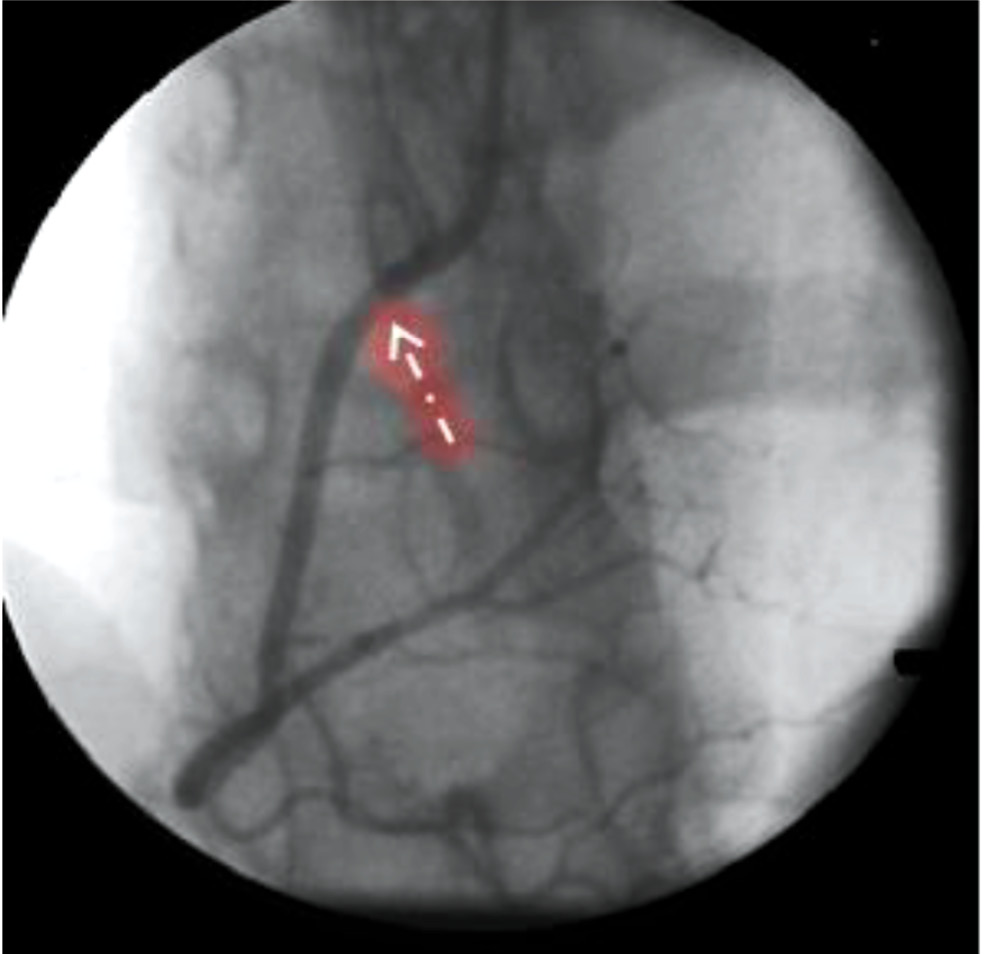

Далее выполнена ангиопластика в зоне диссекции ОВ баллонным катетером 2,0×20 мм под давлением 14 атм. (дважды) с восстановлением антеградного кровотока по ОВ до степени TIMI III. От устья ОВ имплантирован коронарный стент с лекарственным покрытием 4,0×18 мм (EES) давлением 12 атм. При контрольной ангиографии диссекций и резидуального стеноза не обнаружено, кровоток по ОВ её ветвям — со скоростью TIMI III. После была проведена ангиопластика в устье ПМЖА баллонным катетером 2,5×20 мм под давлением 14 и 16 атм., и от устья ПМЖА до устья диагональной ветви ДB имплантирован коронарный стент с лекарственным покрытием 3,0×28 мм (EES) давлением 14 атм. При контрольной ангиографии диссекции и резидуальный стеноз отсутствуют, кровоток по бассейну ПМЖА восстановлен со скоростью TIMI III (рис. 5).

Рис. 5. Контрольная коронарограмма пациентки К. Восстановленный кровоток по ветвям левой коронарной артерии с отсутствием диссекций и резидуальных стенозов.

Fig. 5. Control coronarogram. Restored blood flow through the branches of the left coronary artery with the absence of dissections and residual stenoses.